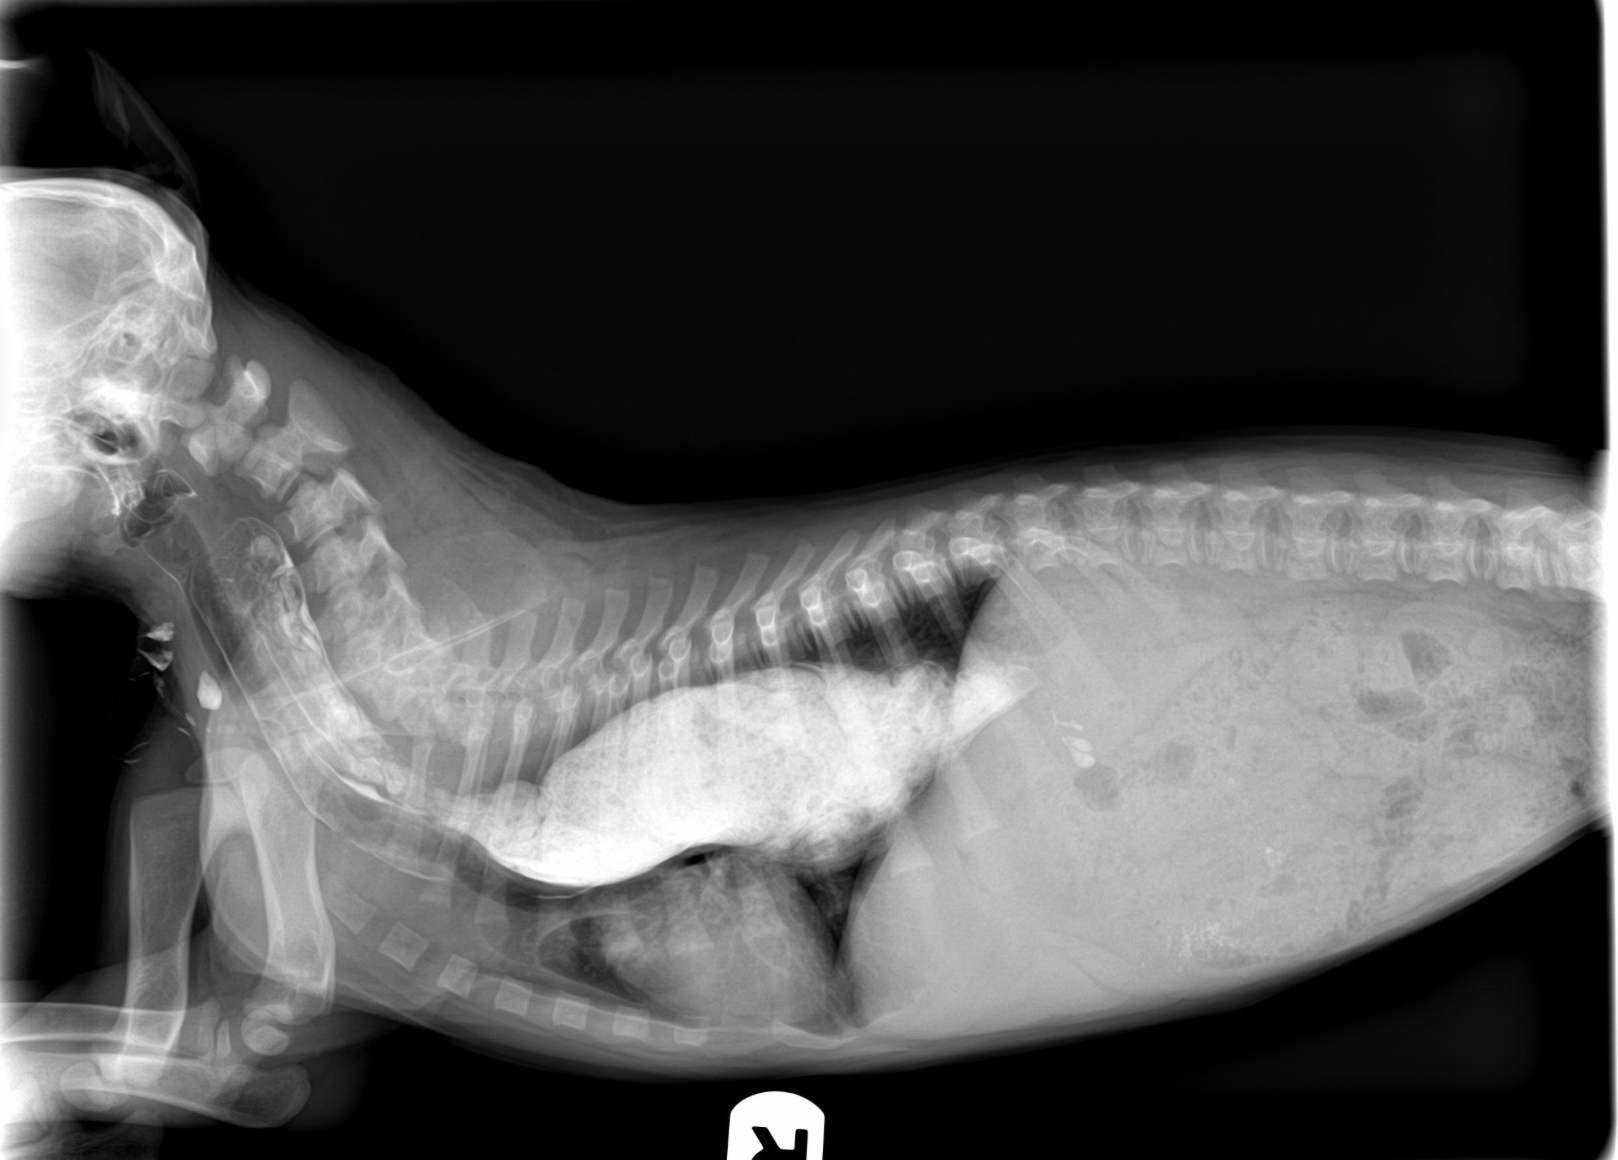

Diagnosis is made by radiographs of the chest. Sometimes positive contrast radiography (as seen below), esophagoscopy or fluoroscopy (real-time xray) may be necessary to make a definitive diagnosis in mild cases.